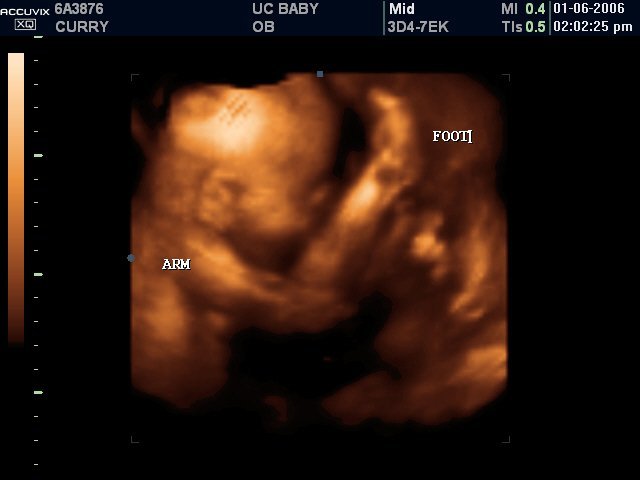

• Development of 3-D

Development of 3-D

3-D ultrasound was developed and 3-D images were captured of a fetus. A 3D ultrasound is acquired by emitting high-frequency sound waves. Researchers in Scotland began working on a multiplanar scanner. As computers developed, a true 3D ultrasound became more feasible. In 1984, the first concrete work on a Japanese 3D ultrasound began, and was successful by 1986. -WiseGeek Reference:

McGuigan, Brendan, and Bronwyn Harris. WiseGeek. Conjecture

http://www.wisegeek.com/what-is-3d-ultrasound.htm

• Development of 4-D (Real Time) / Ultrasound Progression

Development of 4-D (Real Time) / Ultrasound Progression

4-D ultrasound (real time) was developed . Ultrasound guided biopsies were also beginning to develop into everyday practice. Due to the fact that 4D machines create a higher quality image, there is some concern that the energy level used by them may be higher, although this has not been proven. -WG Reference: